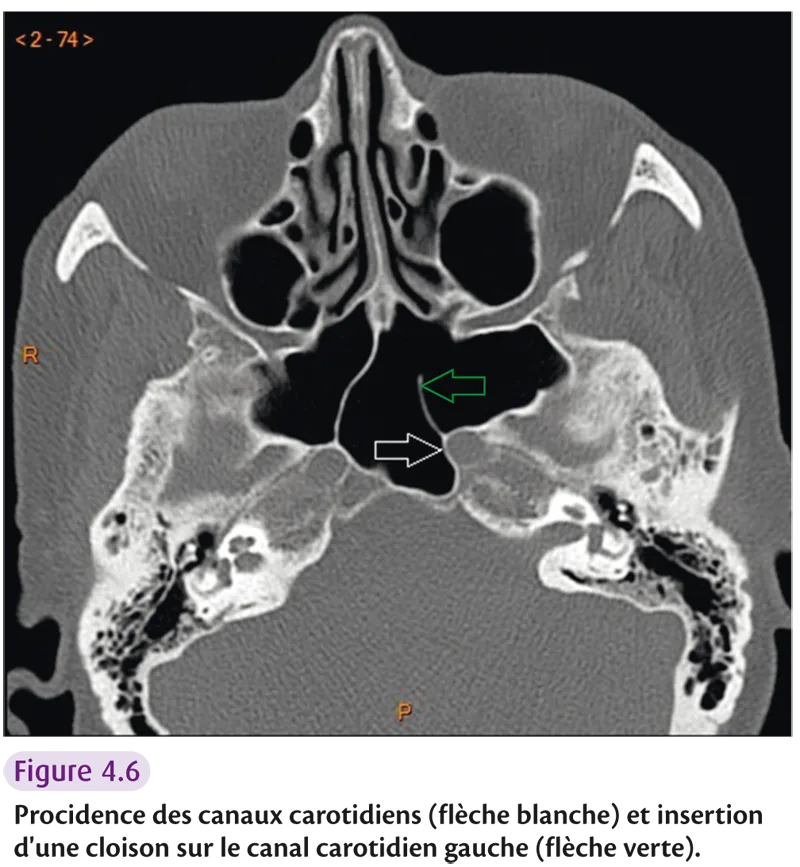

Variantes à risque chirurgical

Risque hémorragique : – procidence de la carotide interne (figure 4.6) ; – insertion d’une cloison du sinus sphénoïdal sur le canal carotidien ; – trajet intra-ethmoïdal de l’artère ethmoïdale antérieure.

Fig 4.6